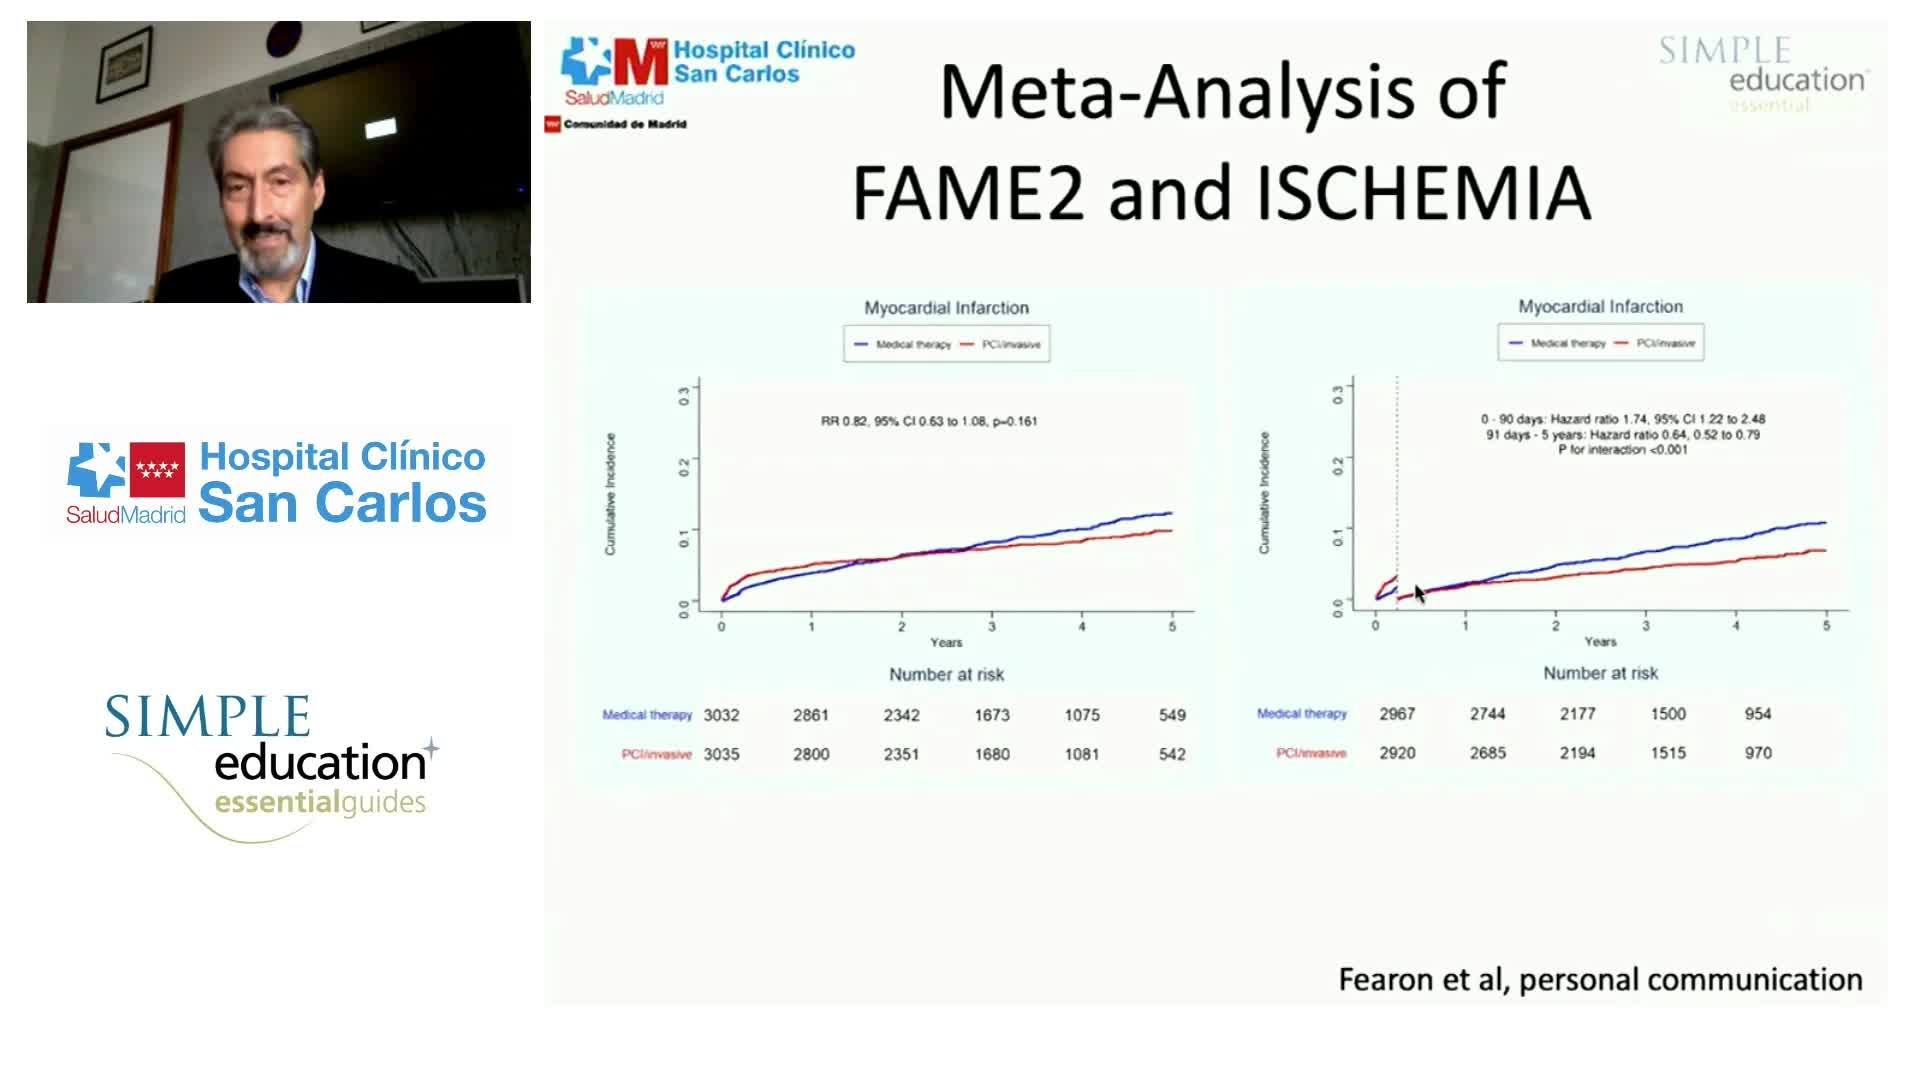

20 year overview of clinical trial data to support the use of coronary physiology in revascularisation decision-making

Best practices and personalised medicine in complex PCI - Prof Javier Escaned

Revascularisation in stable angina: a contemporary perspective - Dr Rasha Al-Lamee